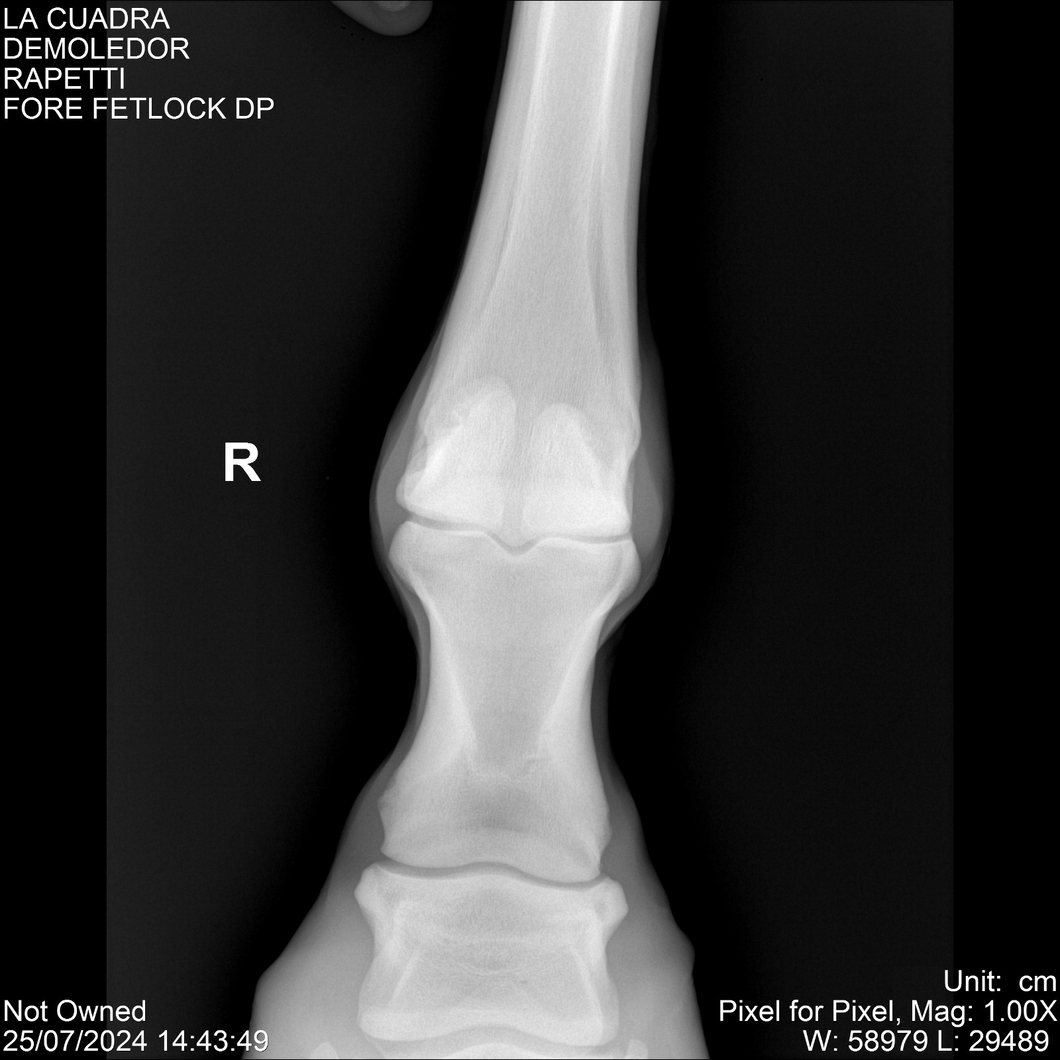

LOTE 14, DEMOLEDOR 🔥 🔥 🔥 Lote Anterior Volver al remate Lote Siguiente Ficha Contacto Montevideo - Ficha del Lote Identificador: #284454 Categoría: Yeguarizos Montevideo - 89 Visualizaciones ClicData Contacto Empresa: Abelenda N. R., Walter Hugo Nombre*: Teléfono* : E-mail* : Mensaje Enviar Registrese gratis Este contenido Exclusivo está disponible sólo para usuarios registrados Ingresar